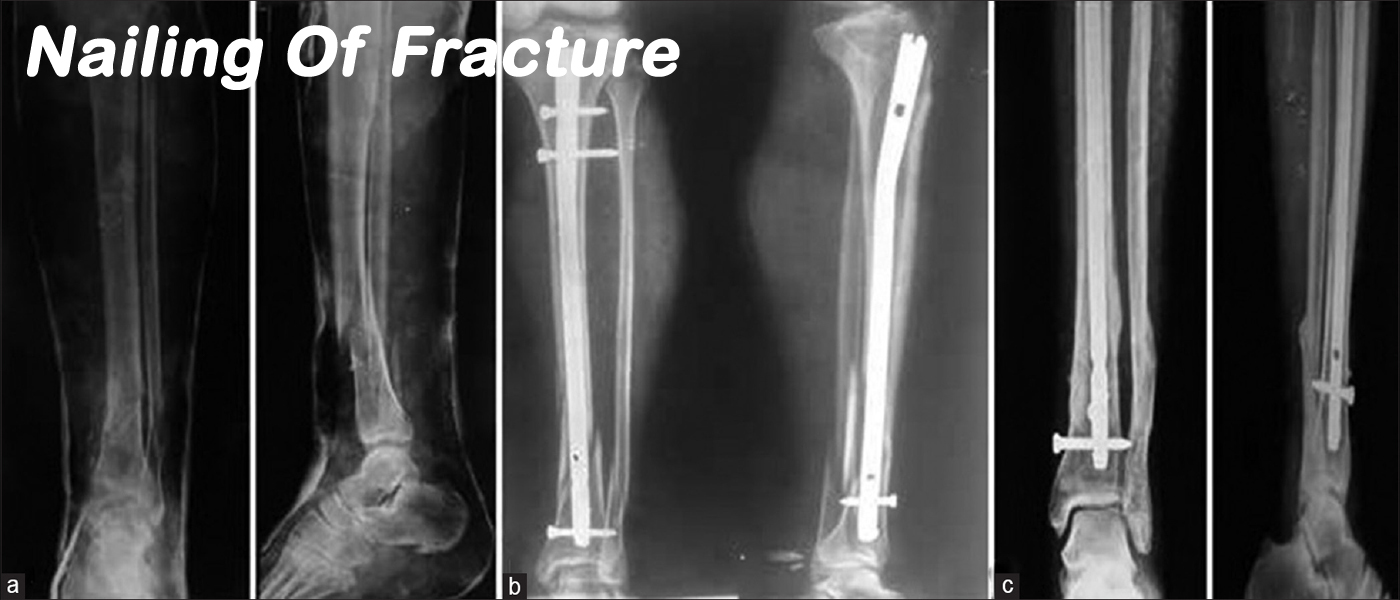

Shreerang Hospital is orthopaedic specialty hospital and is designed specifically for the orthopedic patient. Such a specialized facility and team of experts means we have the utmost in experience and understanding of the needs of orthopaedic patients meaning better outcomes, increased patient satisfaction and a reduced risk of infection or complications. Our goal is to provide you with the ultimate patient experience and excellent outcomes when undergoing orthopaedic surgery. Your care, comfort & peace of mind is constantly our top priority from pre-admission through your surgery & stay at our hospital.

Be the best place for orthopaedic & surgical, Provide quality and accessible orthopaedic & surgical services with the latest technology & equipments.

Our objective to maintain high standards of orthopaedic & surgical treatment, care and surgery. The main objective of the hospital is to offer high quality and more prominent patient care.